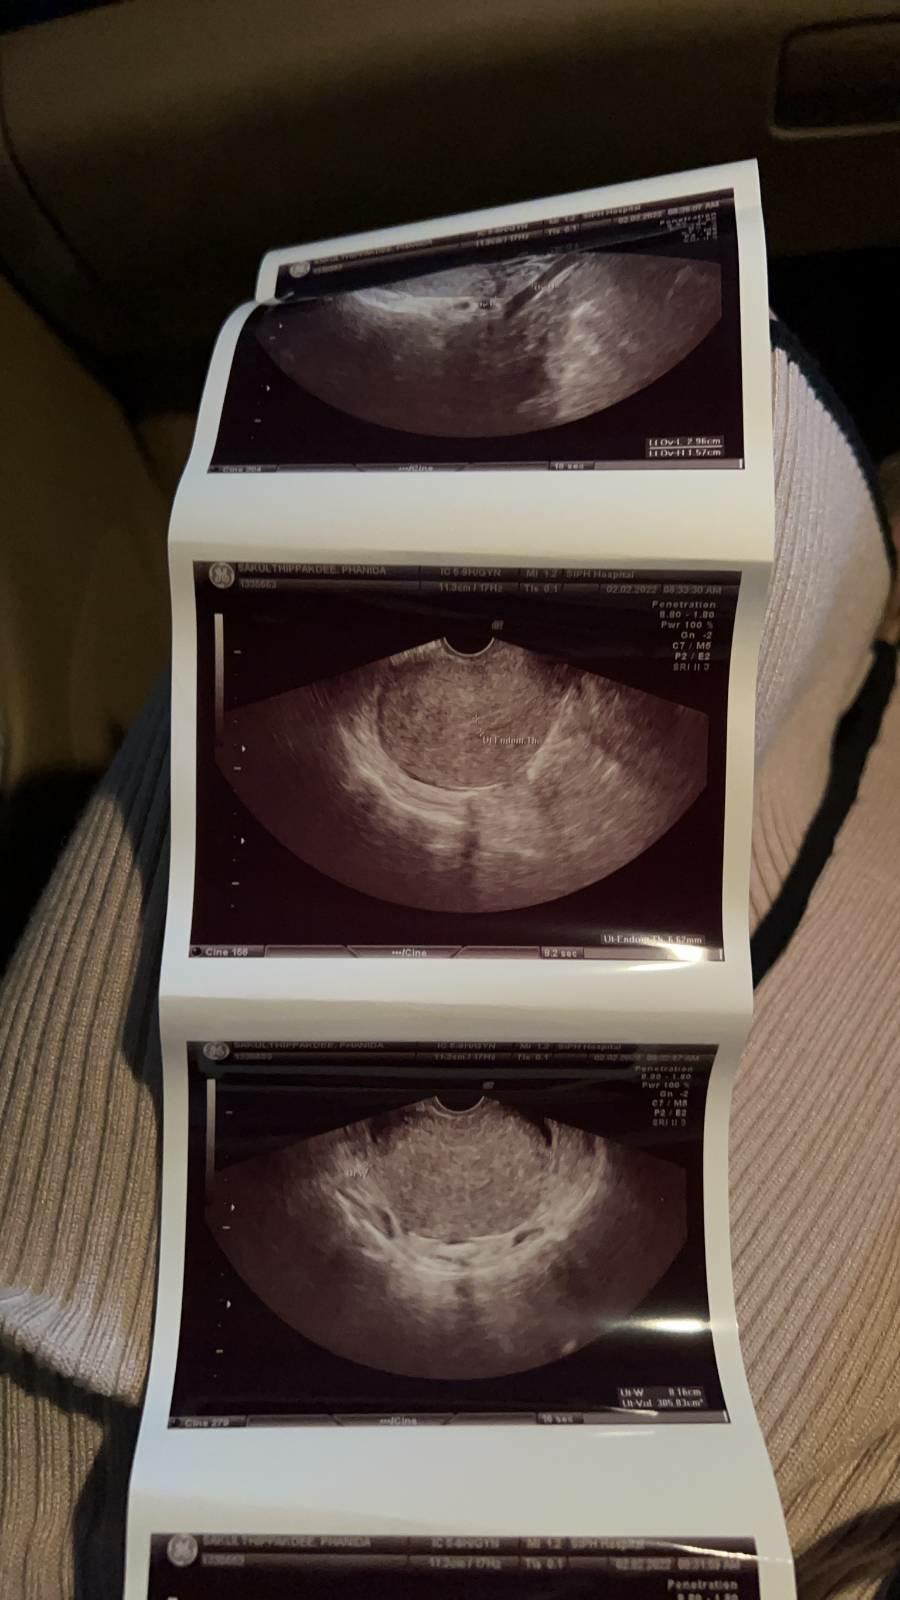

ภาพเอกซเรย์แบบนี้ท้องหรือเปล่า

อยากทราบว่าอันนี้เป็นภาพเอกซเรย์ของคนท้องจริงหรือว่าเป็นภาพเอกซเรย์ของก้อนมะเร็งอะคะ ถ้าถามว่าทำไมถึงคิดว่าเป็นมะเร็งก็คือเรามองเห็นแล้วมันเป็นก้อน ๆ เลยนึกถึงมะเร็งน่ะค่ะ😅😅